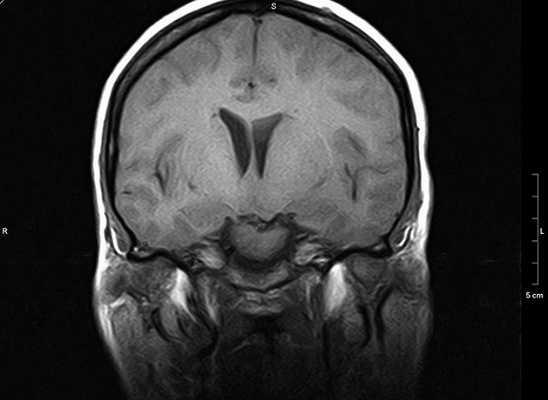

МР-сканирование головного мозга с прицельным изучением мосто-мозжечкового угла, фронтальный срез

«Окрашивающий» раствор заполняет просвет вен и артерий, межклеточное пространство в исследуемой зоне. На снимках появляется четкий рисунок сети кровеносных сосудов, хорошо видны аномалии строения (петли, анастомозы, аневризмы и пр.), определяется зона компрессии корешка черепно-мозгового нерва при вазоневральном конфликте.

При использовании контраста МРТ визуализирует новообразования, диаметр которых не превышает 3 мм. Ткани опухоли накапливают усиливающий препарат, сосудистая сеть, в зависимости от степени малигнизации (озлокачествления), имеет характерный рисунок. На основании полученных изображений рентгенолог может предположить характер процесса, окончательный диагноз ставит лечащий врач.

Магнитно-резонансная томография показывает кисты, абсцессы, гематомы и другие образования с жидким содержимым. Метод отличается высокой информативностью в отношении очагов демиелинизации нервных волокон.